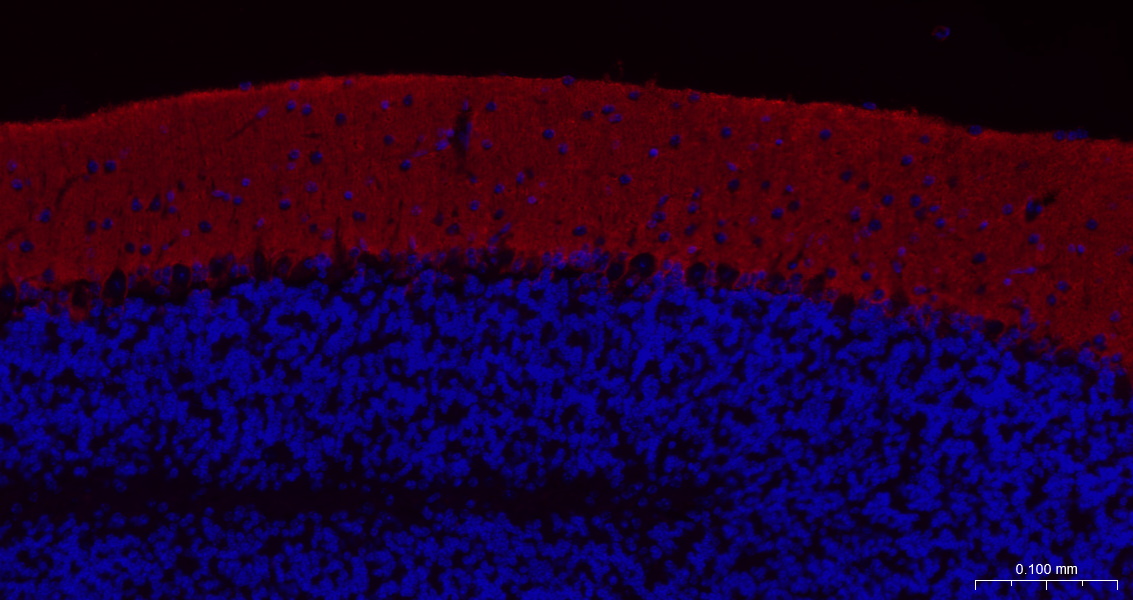

Paraformaldehyde-fixed, paraffin embedded Mouse Cerebellum; Antigen retrieval by boiling in sodium citrate buffer (pH6.0) for 15 min; The section was incubated with EAAT1 Monoclonal Antibody, Unconjugated (bsm-60880R) at 1:200 overnight at 4°C. Followed by conjugated Goat Anti-Rabbit IgG antibody (Red, bs-0295G-BF594), DAPI (blue, C02-04002) was used to stain the cell nuclei.